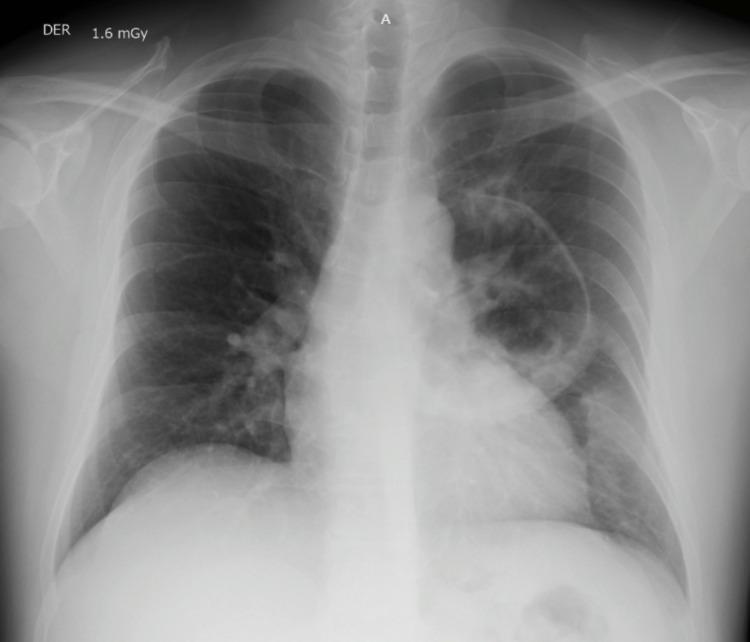

Since the development of antiretroviral therapy (ART) and antibiotic prophylaxis, the incidence of opportunistic infections in human immunodeficiency virus-acquired immunodeficiency syndrome (HIV-AIDS) has been drastically reduced. However, third-world countries remain a fertile ground for medication nonadherence and inappropriate patient follow-up. Here, we present the case of a 42-year-old male with a history of HIV who presented with worsening shortness of breath and atypical chest pain. A chest X-ray and chest computed tomography scan revealed a left parahilar cavitation measuring 86 mm in diameter. A percutaneous lung biopsy revealed . Appropriate antibiotics were started, and the patient's clinical status significantly improved. This case illustrates the devastating consequences of uncontrolled HIV-AIDS. ART and prophylactic antibiotics remain the cornerstone of treatment to ameliorate progressive lung damage in patients.

自从抗逆转录病毒疗法(ART)和抗生素预防措施发展以来,人类免疫缺陷病毒获得性免疫缺陷综合征(HIV-AIDS)中机会性感染的发生率已大幅降低。然而,第三世界国家仍然是药物治疗依从性差和患者随访不当的温床。在此,我们报告一例42岁有HIV病史的男性病例,该患者出现呼吸急促加重和非典型胸痛。胸部X线和胸部计算机断层扫描显示左肺门旁有一个直径86毫米的空洞。经皮肺活检显示……开始使用适当的抗生素后,患者的临床状况显著改善。该病例说明了未控制的HIV-AIDS的毁灭性后果。ART和预防性抗生素仍然是改善患者进行性肺损伤的治疗基石。